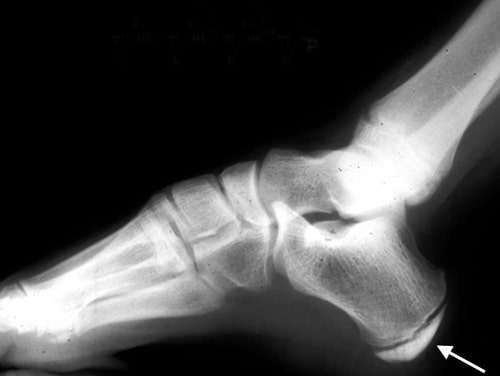

x-ray of Sever's disease

An X-ray of an adolescent foot shows the open growth plate of the calcaneus. The X-ray of a child with Sever's disease usually appears normal, which is why X-ray is not the most reliable imaging test for this condition.

Reproduced from JF Sarwark, ed: Essentials of Musculoskeletal Care, ed 4. Rosemont, IL, American Academy of Orthopaedic Surgeons, 2010.